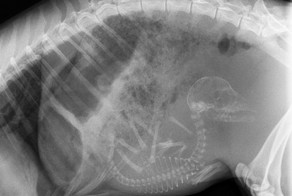

Так выглядят рентгеновские и ультразвуковые снимки беременных животных.

Беременная собака